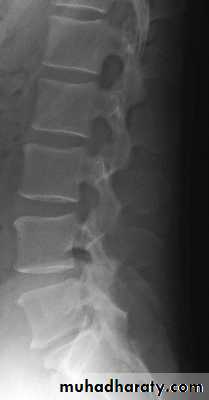

Lumbar Spine X Ray

Lateral radiograph